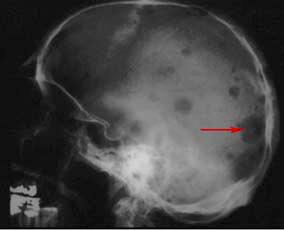

Often, no symptoms are noticed initially. Multiple myeloma is a cancer that begins in plasma cells, a type of white blood cell. This is a form of cancer of the plasma cells that are present in bone marrow. Cancer starts when cells begin to grow out of control. Smoldering multiple myeloma (smm) or asymptomatic myeloma. Multiple myeloma is neoplastic proliferation of plasma cells that commonly results in multiple skeletal lesions, hypercalcemia, renal insufficiency, and anemia. Multiple myeloma (mm) is a debilitating malignancy that is part of a spectrum of diseases ranging from monoclonal gammopathy of unknown significance (mgus) to plasma cell leukemia. It affects cells called plasma cells, which are types of white blood cells. Multiple myeloma treatments include medications and bone marrow transplant. Multiple myeloma (kahler's disease) is a malignant plasma cell dyscrasia characterized by uncontrolled proliferation and the diffuse infiltration of monoclonal plasma cells in the bone marrow. Learn more about multiple myeloma and diagnosis and treatment at memorial sloan. Multiple myeloma is a form of cancer that occurs due to abnormal and uncontrolled growth of plasma cells in the bone marrow. Coronavirus disease programme online course:

3,517 likes · 134 talking about this. Patients typically present at ages > 40 with. Multiple myeloma (also referred to as myeloma) is a type of rare, incurable cancer of the blood—also known as hematologic cancer. In multiple myeloma, abnormal cells circulate and then settle in the marrow or other parts of the skeleton, where. Multiple myeloma is neoplastic proliferation of plasma cells that commonly results in multiple skeletal lesions, hypercalcemia, renal insufficiency, and anemia. People who are diagnosed with smm have higher levels of m protein and more plasma cells in the bone marrow than people with. Multiple myeloma is a blood cancer affecting plasma cells. Multiple myeloma is a cancer that forms in a type of white blood cell called a plasma cell. Bone marrow is the spongy tissue at the centre of some bones that produces the body's blood cells. Smoldering multiple myeloma (smm) or asymptomatic myeloma. Multiple myeloma is cancer that starts in the bone marrow's plasma cells. Multiple myeloma is a type of blood cancer that affects plasma cells — learn about diagnosis multiple myeloma can be a highly manageable disease. Some people with multiple myeloma, especially those with early stages of.